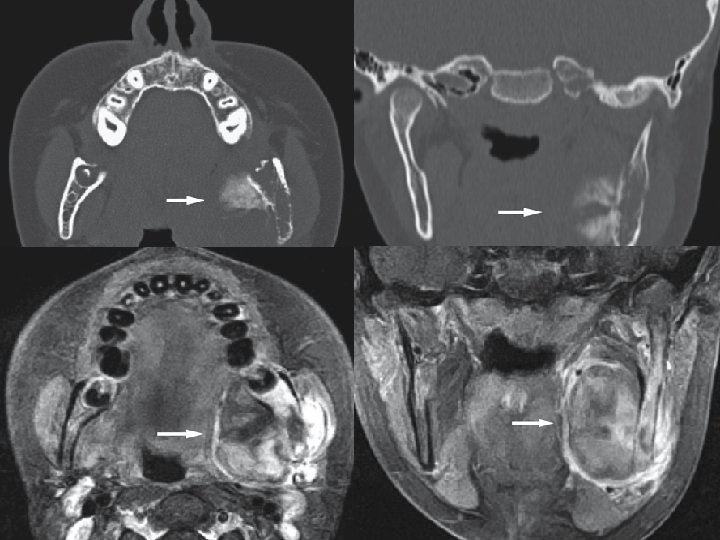

Coronal CT image Coronal T 2 - fat suppressed MRI Squamous cell carcinoma, maxilla; 70 -year-old female with some bleeding from tender soft tissue mass of right gingival mucosa.